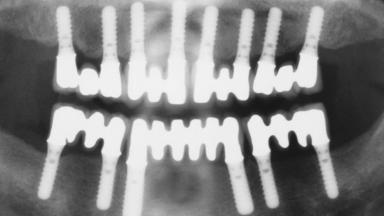

Immediate Loading of Eight Implants in the Maxilla and Six Implants in the Mandible and Final Restoration with Three-Unit and Four-Unit FDPs

# of Implants 14

Type of Implants One-Piece

Defining Characteristics Fully edentulous upper jaw to be rehabilitated with four or more implants

Modality 6+ implants with immediate loading

Bone Volume Horizontally and vertically sufficient

Defining Characteristics Fully edentulous upper jaw to be rehabilitated with an implant-borne fixed dental prosthesis